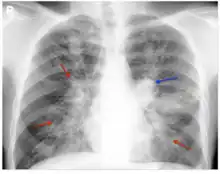

The chest radiograph of an allergic bronchopulmonary aspergillosis patient shown with left-sided perihilar opacity (blue arrow) along with non-homogeneous infiltrates (transient pulmonary infiltrates indicated by red arrows) in all zones of both lung fields.